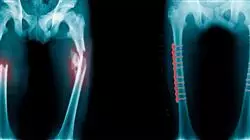

Quando un bambino presenta dolore al ginocchio, è importante che lo specialista monitori la sua situazione. Sapere cosa sta causando disagio sarà fondamentale per ricevere il trattamento adeguato. Alcune delle patologie del ginocchio più comuni nei bambini sono gonfiori, fratture, distorsioni, tendinite, rottura del menisco, borsite o lesioni da sovraccarico.

Questo Corso Universitario è ideale per lo studente per aggiornare le loro conoscenze sulle caratteristiche cliniche, radiologiche ed epidemiologiche della malattia di Osgood-Schlatter o identificare i possibili segni di allarme di tale patologia. Inoltre, approfondirà le lesioni osteocondrali nei bambini, approfondirà le implicazioni della rottura del legamento crociato e gestirà le fratture intorno al ginocchio, tra gli altri aspetti.